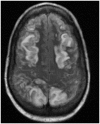

Results: Eight out of the 20 patients included in the study were on cyclosporine or tacrolimus based immunosuppressant therapy for kidney transplant. Four patients had severe hypertension at presentation. The most common MRI finding was high T2-fluid-attenuated inversion recovery (FLAIR) signal in the cortex and subcortical white matter of both cerebral hemispheres, particularly in the parietal and occipital lobes (n=16). The second most common MRI finding was increased leptomeningeal FLAIR signal (n=7). Out of seven patients with leptomeningeal signal, five demonstrated leptomeningeal enhancement as well. Four out of these seven patients had no other parenchymal findings.